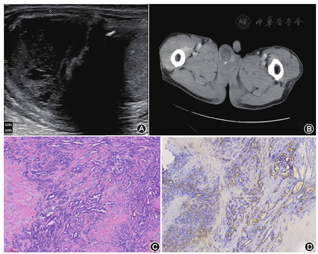

患者,68岁。2018年11月5日因外伤后体检发现右侧阴囊内肿物就诊。既往无阴囊疼痛,无阴囊皮肤发红、发热,无尿频、尿痛等。查体:右侧睾丸上极可触及无痛性肿块,质较硬,大小约2.5 cm×2.0 cm,压痛阴性,不活动。实验室检查:肝功能、凝血功能、前列腺特异性抗原、糖类抗原199、癌胚抗原、甲胎蛋白、人绒毛膜促性腺激素、促黄体生成素、促卵泡激素均正常。阴囊B超:右侧睾丸上方见混合性团块,大小约2.7 cm×2.2 cm,边界可见,未见明显血流信号(图1A)。胸部CT检查:两肺下叶少许絮片状密度增高影,余肺野清晰,未见纵隔淋巴结肿大,未见胸腔积液征象。腹部CT检查:肝、胆、胰、脾未见明显异常。左肾小囊肿。腹膜后区未见肿大淋巴结影。盆腔CT检查:右侧阴囊内见2枚类圆形影,1枚呈稍低密度影伴周边点状钙化,其旁见斑片状稍高密度影;1枚与左侧阴囊内睾丸密度相仿;盆腔未见肿大淋巴结(图1B)。术前诊断为右侧阴囊肿物(性质待查)。行右侧阴囊探查术,术中见右侧肿物与睾丸分界不清,考虑右侧睾丸肿瘤。术中与患者家属沟通,患者无生育要求,不接受睾丸部分切除术可能风险,要求行根治性睾丸切除术。术后病理检查,右睾丸与肿物分界不清,肿物大小约2.7 cm×2.1 cm,质硬,肿瘤切面呈灰白色;睾丸旁小灶腺癌(最大直径0.6 cm),考虑为睾丸网起源,生长形态呈不规则腺管状和乳头状(图1C),细胞异形性明显,核质比增大,可见较多核分裂象和病理性核分裂象,伴陈旧性血肿和血肿壁纤维组织增生,慢性炎,睾丸曲细精管轻度萎缩,附睾和输精管无明显改变,切缘阴性。免疫组化染色检查:CK(-),EMA(+)(图1D),SMALL4(-),WT-1(核-),AFP(-),Vim(+),calretinin(少量+),CD31(少量+),CD34少量()+,Ki-67(约20%+),CD10(-),CD15(少量+),CEA(-),CAM5.2(-),Inhibin(少量+),CD68(+),CK(少量+),CD117(少量+)。病理诊断为右睾丸网腺癌。患者术后拒绝腹膜后淋巴结清扫术(retroperitoneal lymph node dissection,RPLND)和辅助放化疗。术后8个月复查CT发现肺、肝脏、胸椎、肋骨、腰椎、骨盆及腹膜后淋巴结多发转移,术后15个月死亡。